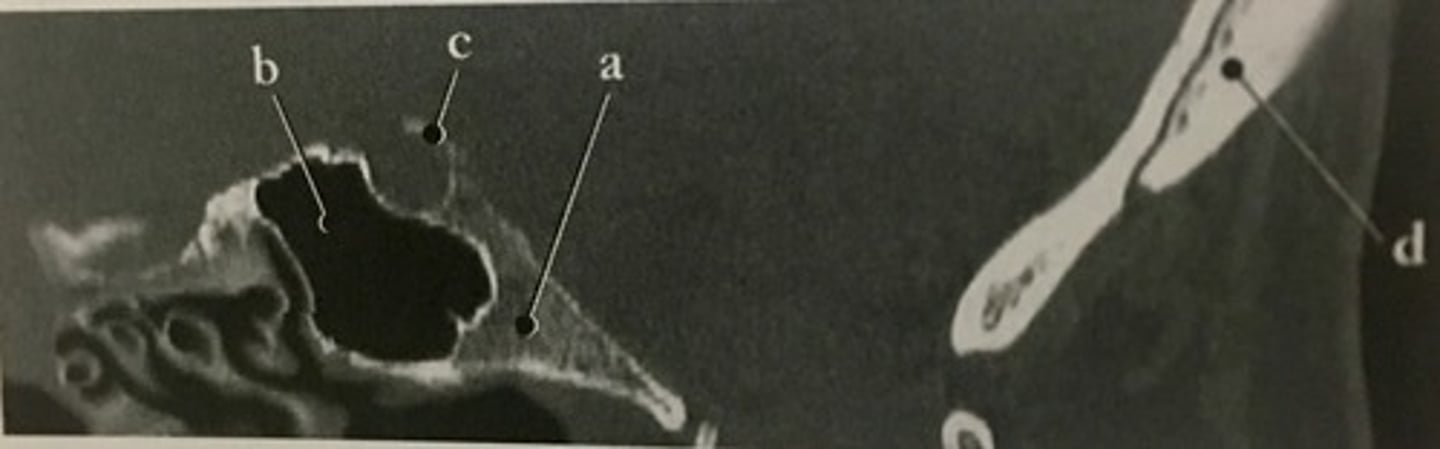

Sphenoid sinus

Identify structure B on this sagittal reformat of the occipital bone.

<p>Identify structure B on this sagittal reformat of the occipital bone.</p>

Semicircular Canal

Number 2 corresponds to which of the following?

<p>Number 2 corresponds to which of the following?</p>

Number 4 corresponds to which of the following?

<p>Number 4 corresponds to which of the following?</p>

External Auditory Meatus

Number 3 corresponds to which of the following?

<p>Number 3 corresponds to which of the following?</p>